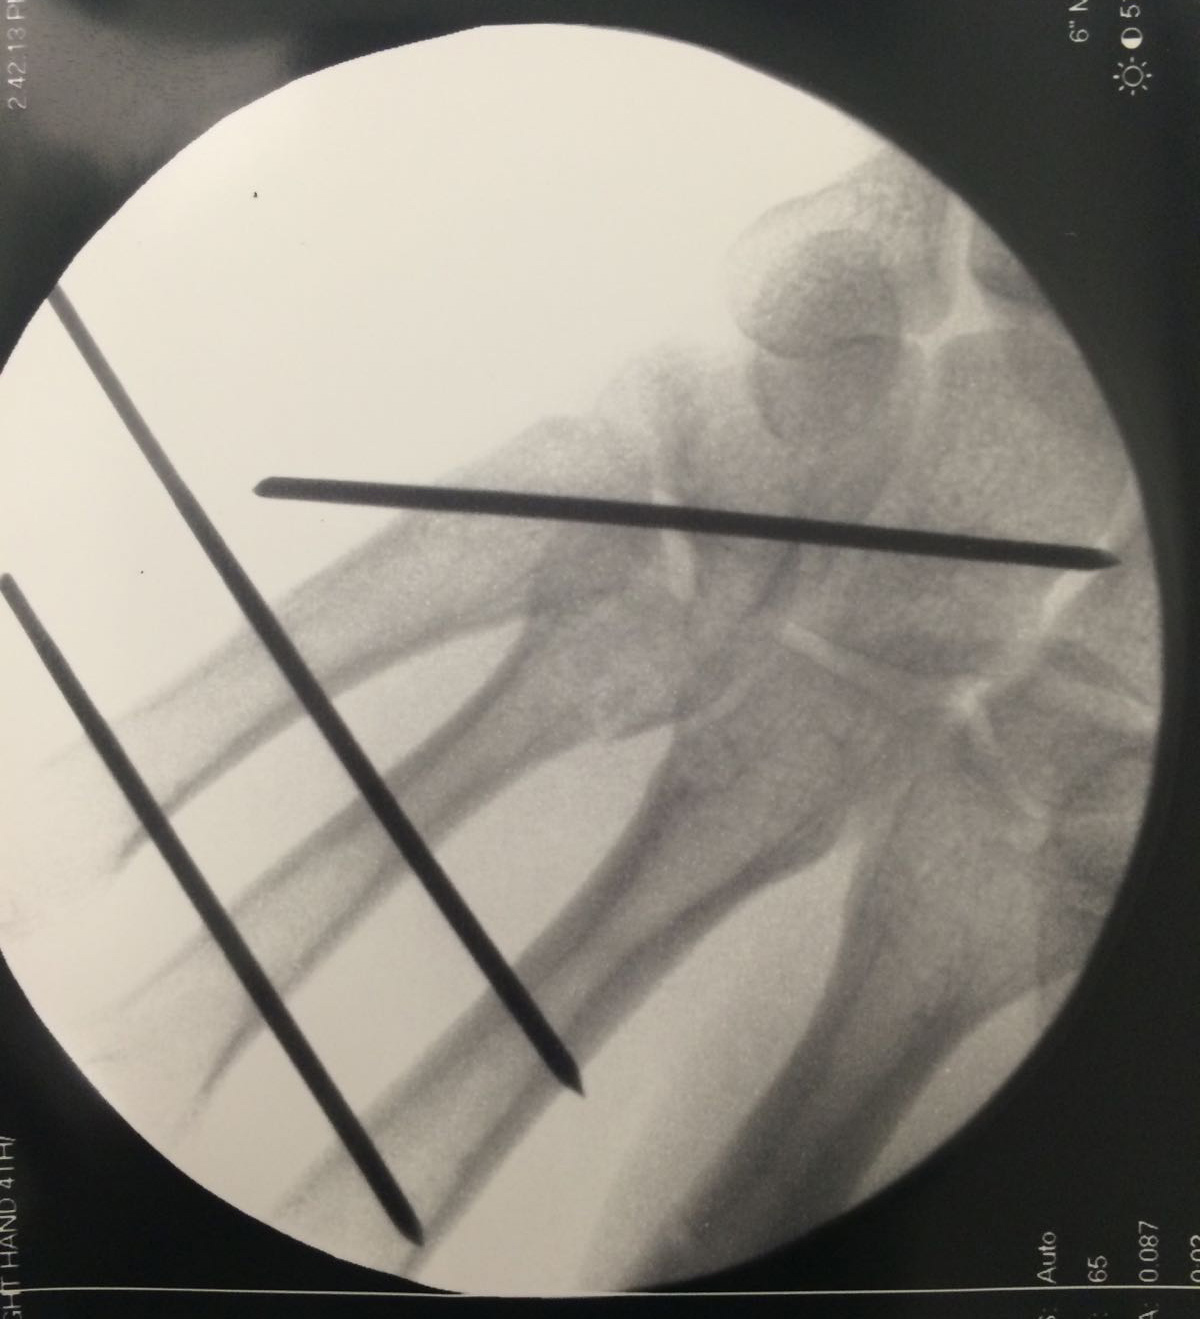

Cette radiographie au bloc opératoire a permis de vérifier la stabilisation par 3 broches qui seront enlevées après 6 semaines.